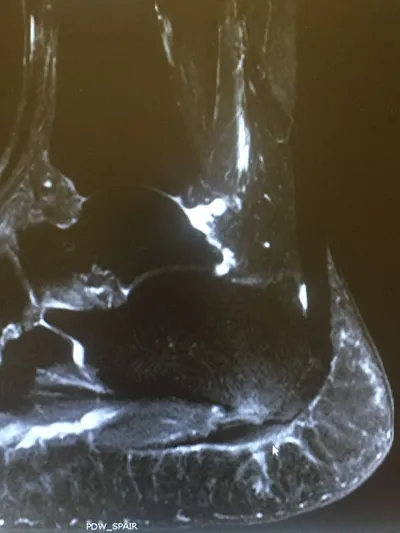

MRI of Severe Plantar Fasciitis of the Medial and Central Band. The bands of the plantar fascia are thickened and there is swelling around the soft tissue of where the fascia inserts in the heel as well in the heel bone itself. On this MRI, the white is inflammation.The arrow points to the thickend and inflammed ligament.